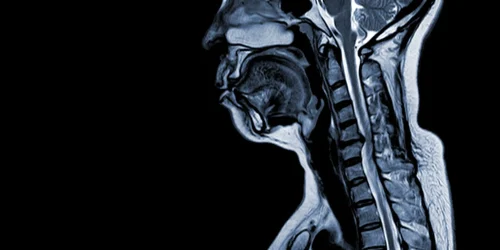

Receiving a cervical spine MRI report can feel like being handed a manuscript written in a foreign language. You see…